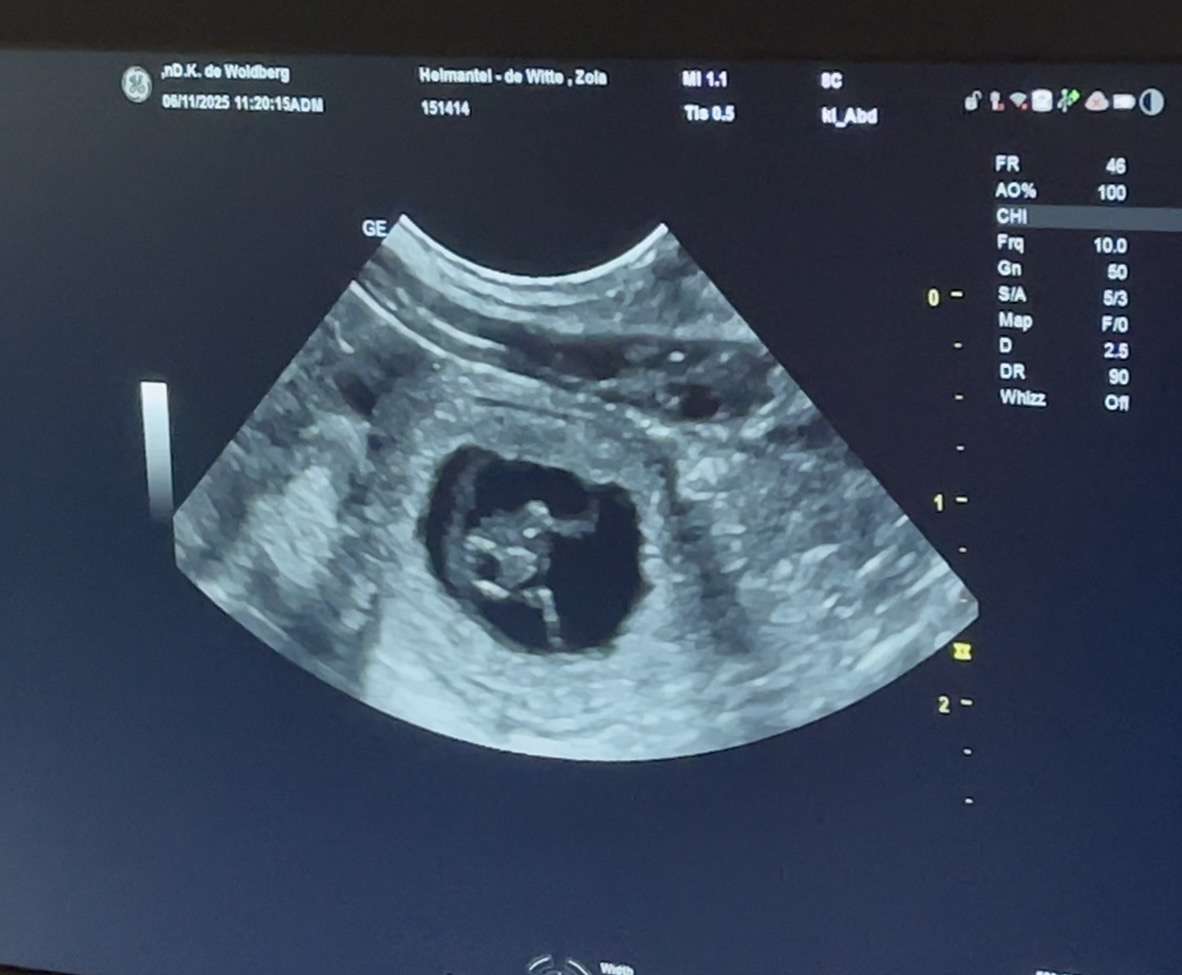

06-11-2025; Super goed nieuws want vandaag hadden we een prachtige echo met Zola!! Ze is drachtig en we verwachten rond 12-12 weer basenji puppies🤩